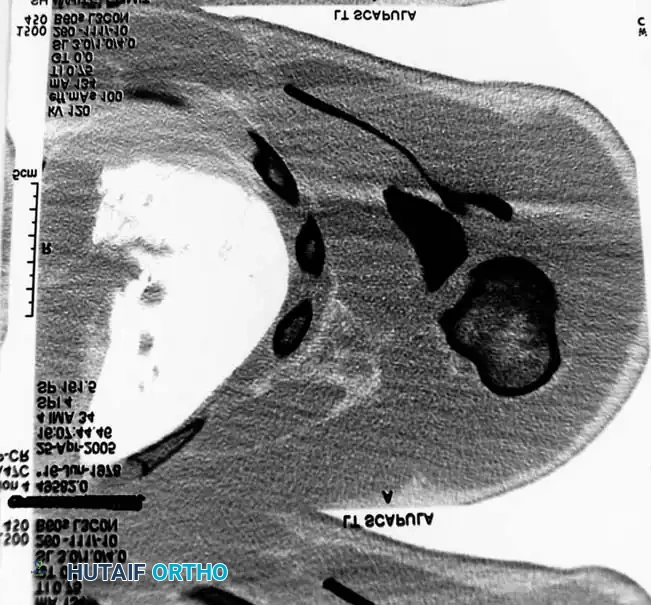

Fig. 54-3B: Axial CT scan detailing the severe displacement of the scapular body and neck.

Fig. 54-3C: Additional axial CT slice confirming intra-articular extension and comminution.